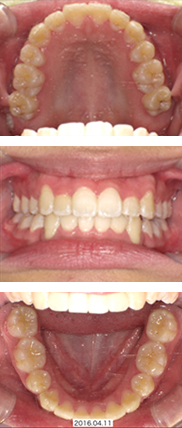

インビザライン症例(前歯のみ動かすマウスピース矯正)

治療費用:33,000円+66万円+5,500円×10+55,000円(リテーナー)

マウスピースの中にホワイトニング剤(6,600円)を入れることで、同時にホームホワイトニングを行いました。

矯正前

矯正中(約6ヶ月後)

矯正後(約4ヶ月後)